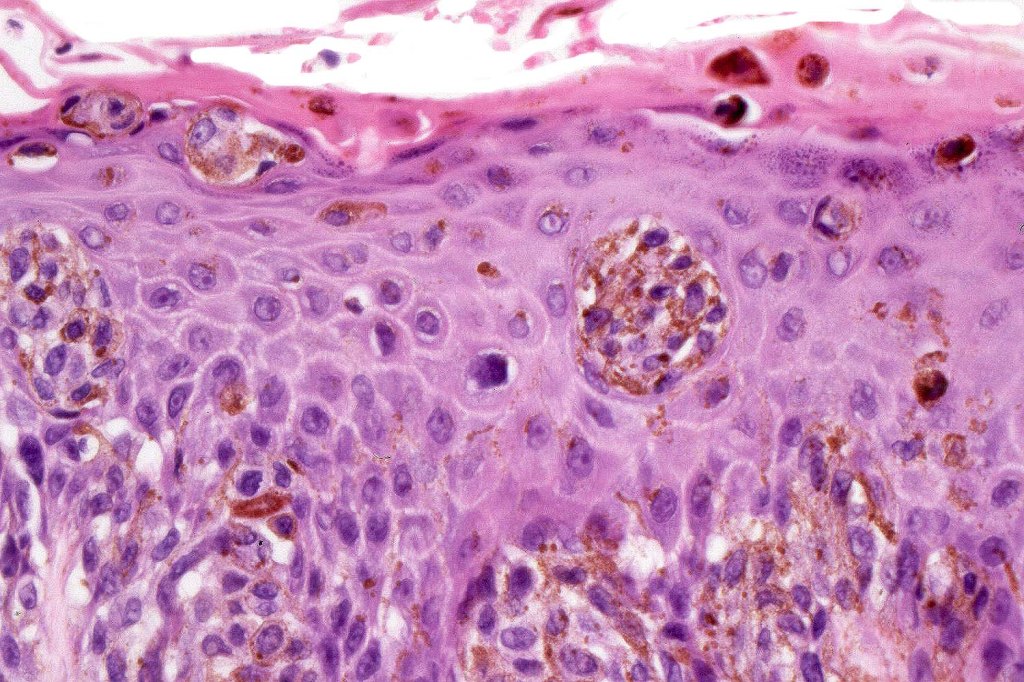

•Central pagetoid spread

•Superficial dermal atypia

•Junctional mitoses sometimes present, dermal mitoses+/-, can be multiple but never atypical

. HMB45 shows gradation with depth, Ki67 is low

Most important is melanoma. Distinction is best afforded by the site of the nevus and the patient’s age. Vulval melanoma is generally a tumor of the elderly. Atypical genital nevus occurs in girls and young women.

There can be overlap with dysplastic nevi although the typical architecture of the latter is absent. Large, heavily pigmented, dyscohesive nests with a retraction artifact point towards atypical genital nevus. Knowing the site of the nevus is all important.